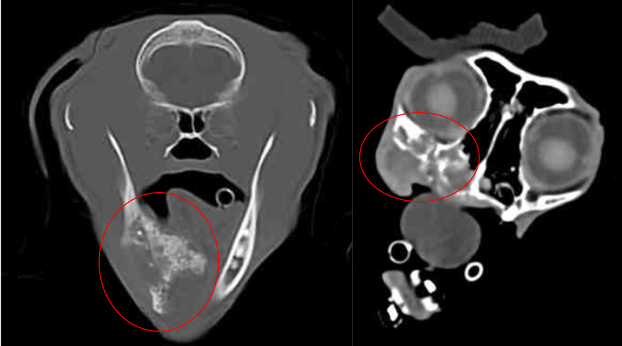

Courtesy of the University of Missouri

Left: FOSCC tumor causing destruction and production of bone in the mandible. The mass extends under the tongue.

Right: FOSCC tumor in the maxilla causing destruction of the bones under the eye and extends to the nasal passages.